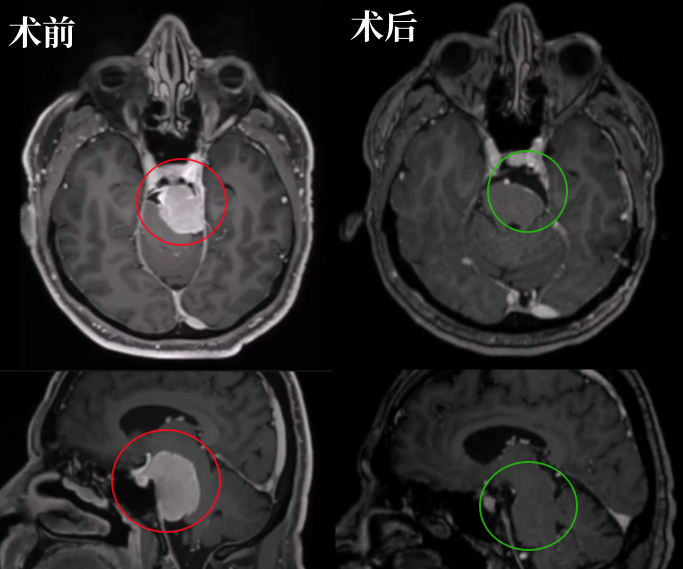

54岁男性Bruno,也是岩斜区脑膜瘤,但是他就没那么幸运了。左侧脸部如刀割般疼痛,甚至还出现吞咽困难,无法进食、难以入眠、无法工作……

2014年,查出岩斜区脑膜瘤,考虑到这是个良性肿瘤,且手术治疗有风险,他选择了保守观察。然而,6年时间,肿瘤持续增长,压迫脑干,症状不断恶化。

福教授采用开颅手术,术前通过线圈在咽升动脉处进行栓塞,可以显著减少术中出血。在切除肿瘤过程中,使用CUSA刀对肿瘤逐渐减瘤。术后MRI显示肿瘤几乎完全切除,脑干受压解除。